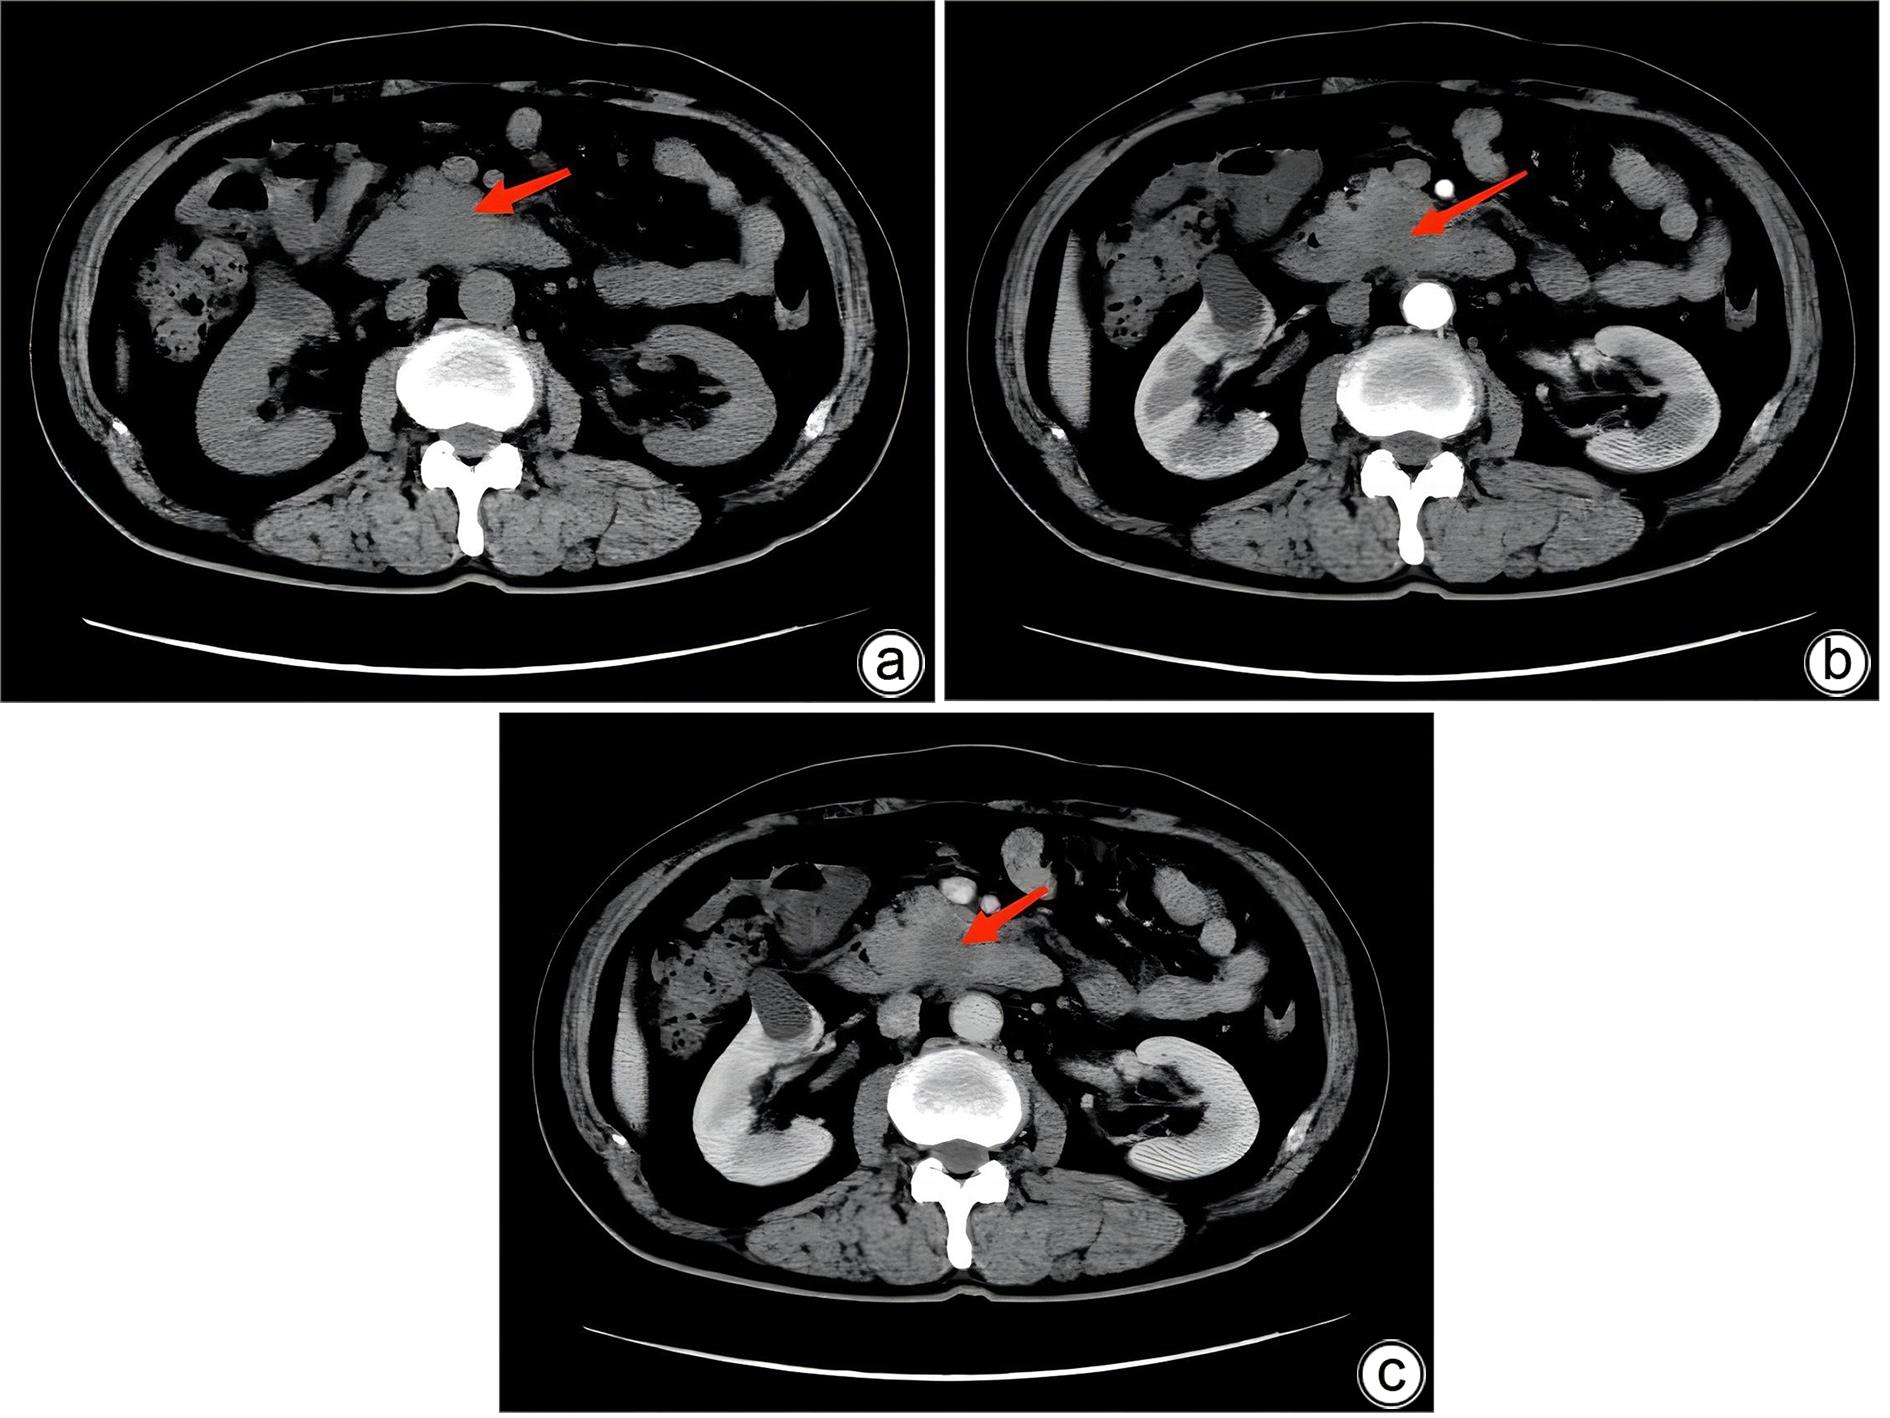

Misdiagnosis of intrapancreatic accessory spleen: A report of two cases

Mengzhe ZHANG, Jie RAO, Zhengle ZHANG

2024, 40(2): 365-368. DOI: 10.12449/JCH240223

Abstract(1274) HTML (315) PDF (1188KB)(59)

Abstract:

Accessory spleen refers to the spleen tissue that exists outside of the normal spleen, with a similar structure to the main spleen and certain functions. Intrapancreatic accessory spleen (IPAS) completely enveloped by the pancreas has an incidence rate of only 2%, and it is easily misdiagnosed in clinical practice due to its atypical clinical symptoms and similar radiological features to pancreatic neuroendocrine tumor, pancreatic solid pseudopapillary tumor, and other pancreatic space-occupying lesions. This article reports the clinical data of two patients with IPAS who were misdiagnosed as pancreatic neuroendocrine tumor and pancreatic solid pseudopapillary tumor, respectively, analyzes the reasons for misdiagnosis, and summarizes the experience in diagnosis and treatment, in order to improve the ability for the differential diagnosis of IPAS in clinical practice.